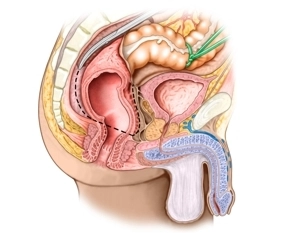

Topografía lateral del recto

![Topografía lateral del recto]()

La fascia de Denonvilliers envuelve en el hombre la pared posterior de la vejiga, las vesículas seminales y la pared posterior de la próstata